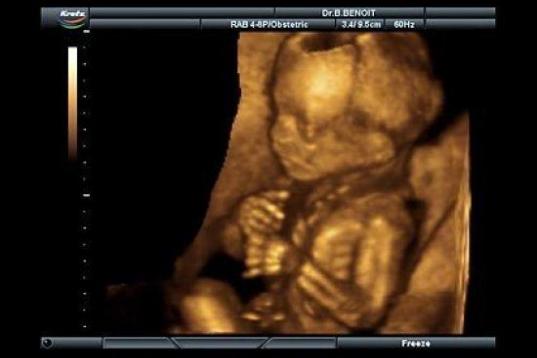

En esta galería puedes ver en fotos como es el desarrollo de un feto de semana en semana:

Desarrollo del feto, en fotos